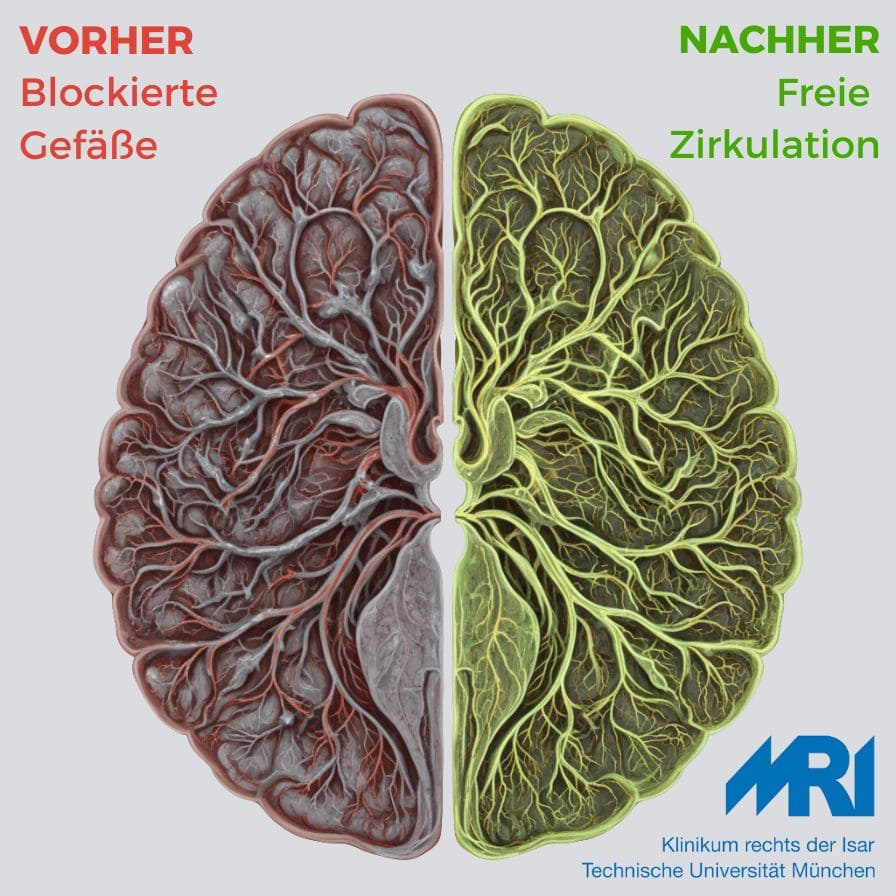

So ändert sich die Gehirnleistung nach 12 Wochen

Aufnahmen aus dem Testverlauf

*Basierend auf durchschnittlichen Ergebnissen von Studienteilnehmern

Sie haben es im Test gesehen: 600 Kilometer feinste Gefäße in Ihrem Gehirn. Vermutlich Verklebt. Teilweise Verstopft. Blockiert.

- München Klinikum Rechts der Isar: „Signifikante Verbesserung der Mikrozirkulation“